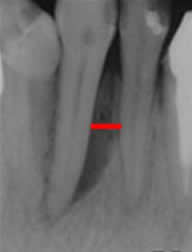

Los dientes se fijan al hueso, por el ligamento periodontal, que es visto como una capa delgada radiolúcida entre la superficie de la raíz (Cemento) y la lámina dura. (1, 4, 8). Su amplitud varia entre 1.3 y 3.8 mm. (15). (Fig 14).

Las raíces de los dientes, están rodeados por el espacio periodontal, que puede ser reconocido en el TAC. Su ensanchamiento, siempre indica patología. (4, 6). (Fig 15).

Fig 15. Espacio periododontal.

Rx periapical. Incremento del espacio que rodea el diente, por enfermedad periodontal.